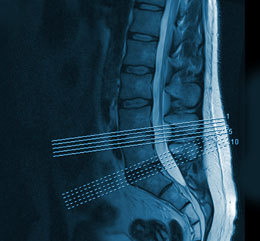

Für Privatpatienten führen wir MRT-Untersuchungen an einem Standort außerhalb der Praxis regelmäßig selbst durch. Hierfür ist ein Arzt aus unserer Praxis vor Ort anwesend und wird das Ergebnis direkt im Anschluss an die Untersuchung mit Ihnen besprechen.